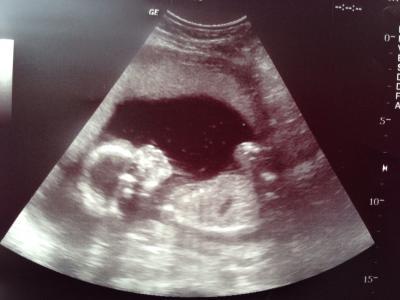

War ja auch heut Mittag beim FA...alles super mit dem kleinen Krümel, richtig groß schon mittlerweile und hat sich mal wieder in eine extra Foto-Pose geworfen. Vermessen wurde nix großartig da ich eh in 12 Tagen zur Feindiagnostik gehe. Sie meint relativ sicher dass es ein kleiner Junge wird, was überhaupt nicht schlimm ist für mich, aber ich hatte u habe wirklich dass Gefühl es wäre ein Mädchen. Kennt das jemand oder kennt jemand jemanden bei dem es auch erst ein Junge war und dann doch ein Mädchen? Warten wir mal ab was zur Feindiagnostik geschlechtsmässig raus kommt. Bin sehr fasziniert von dem kleinen, sooo süß und fein hat es sich benommen